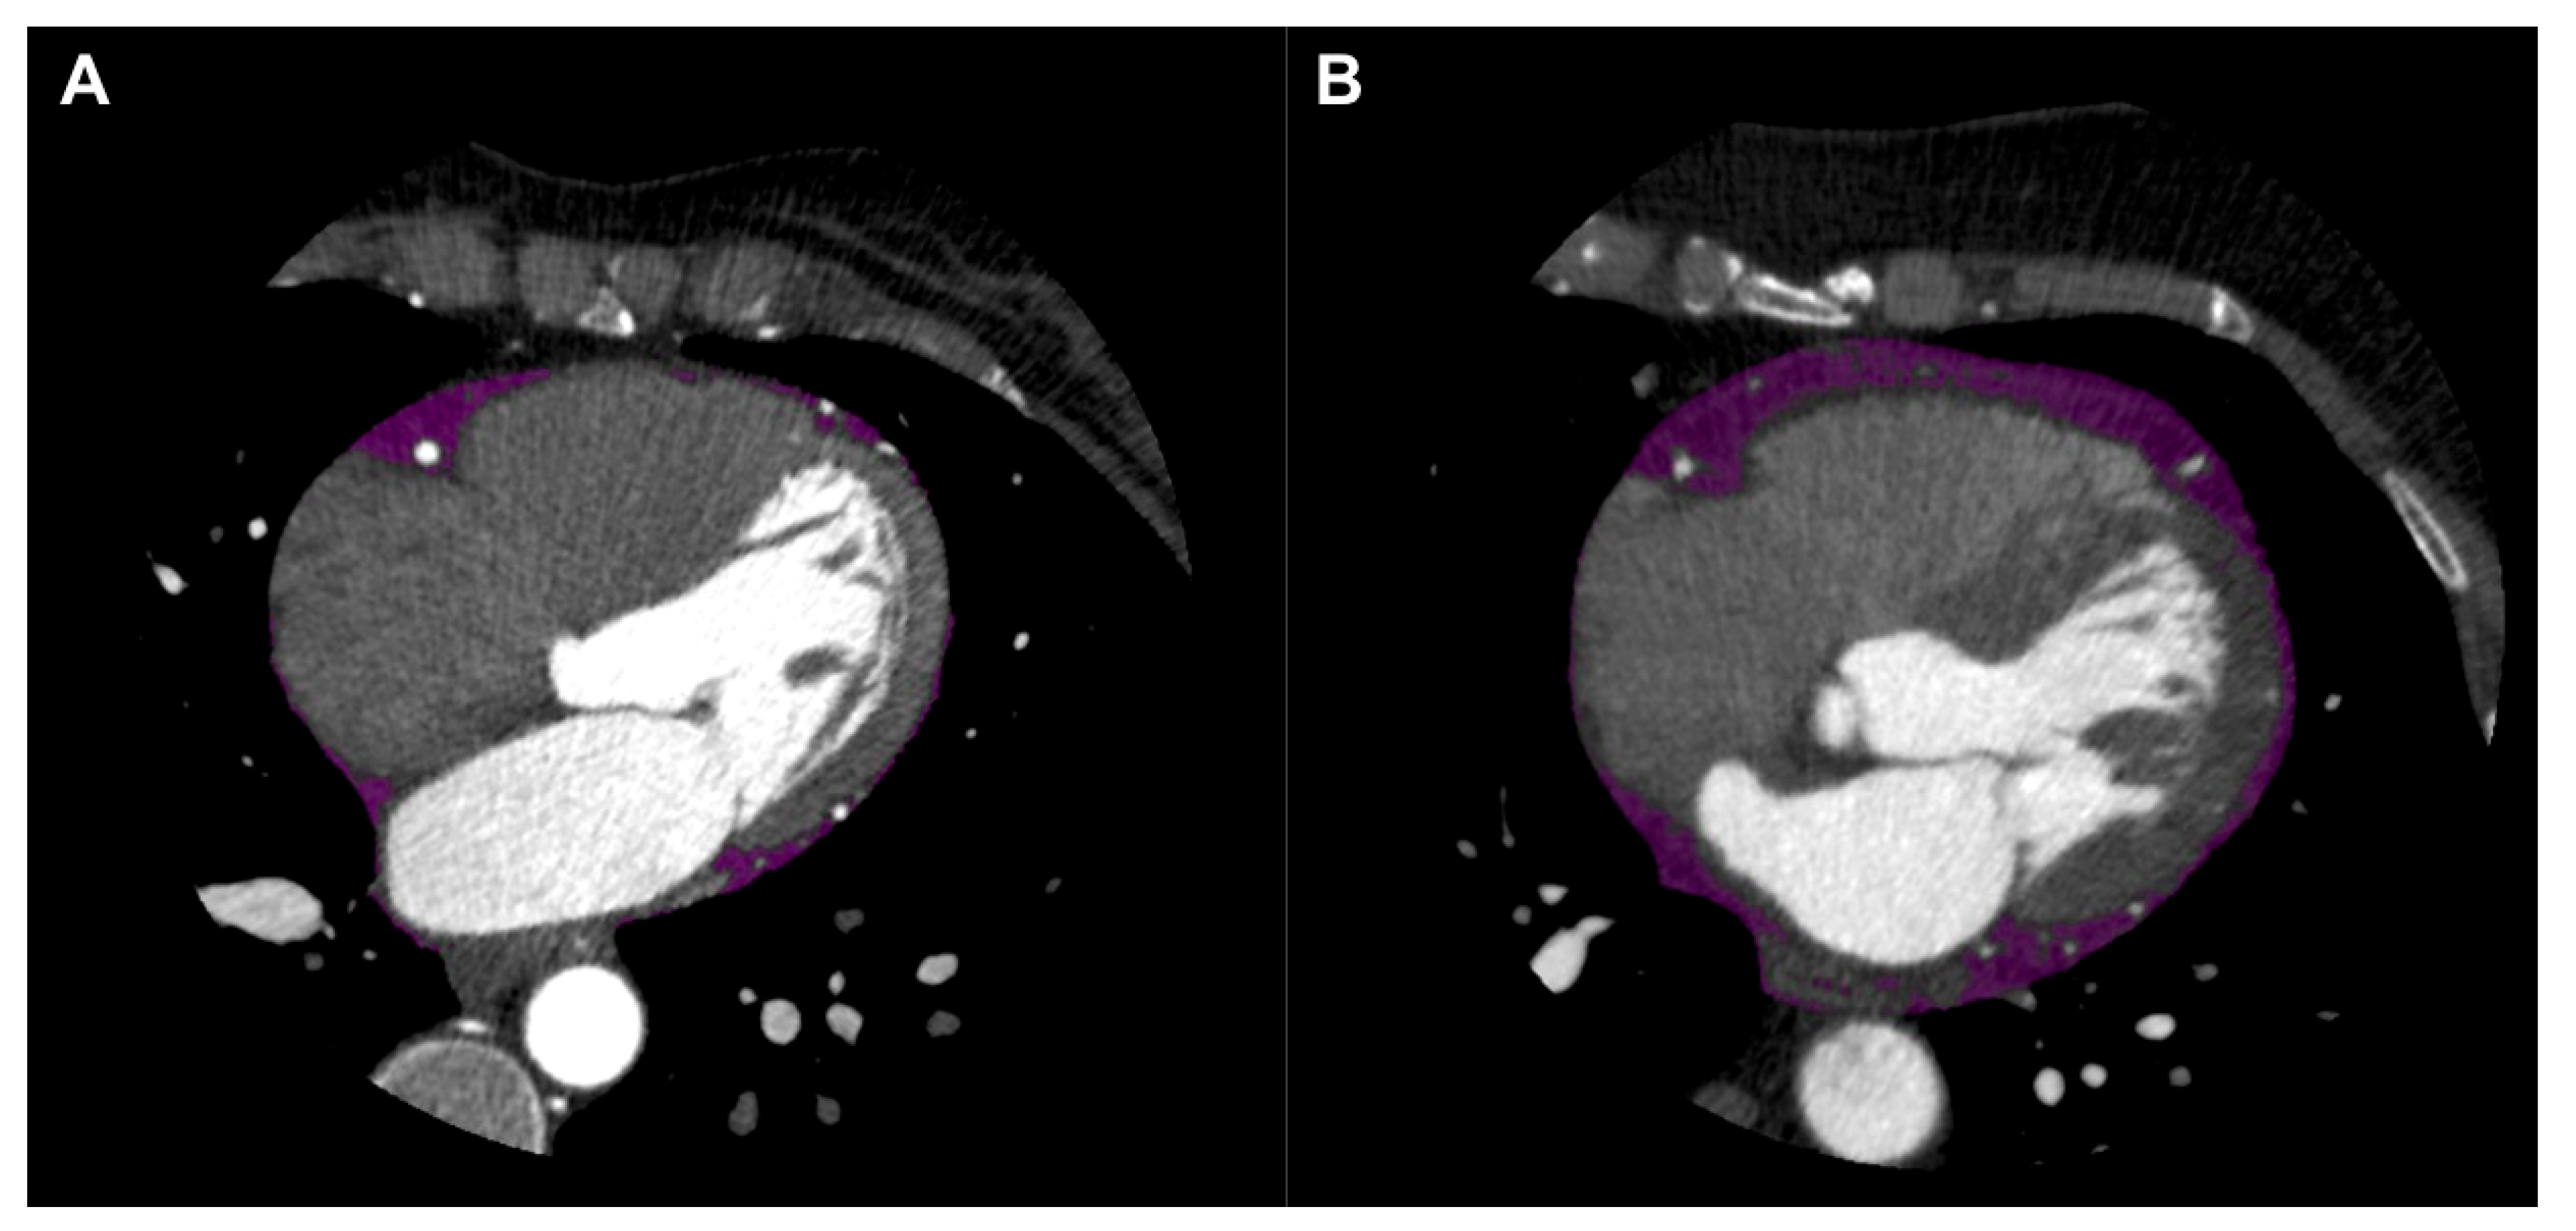

5.1. EAT Quantification